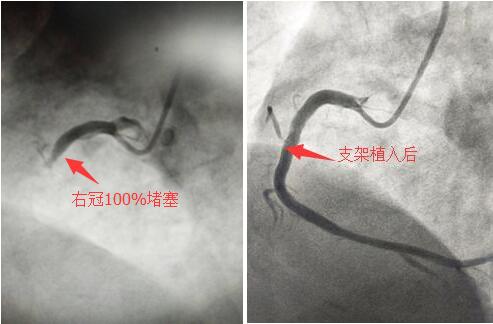

5月10日晚上19時(shí),心內(nèi)科導(dǎo)管室剛剛結(jié)束一例急性下壁心?;颊叩氖中g(shù),宋宜生副主任還沒來得及脫下沉重的鉛衣,“叮鈴——”一陣急促的電話鈴聲響起,“宋主任,急診科送來一例急性心梗的患者!”他立即把白大褂套在已經(jīng)被汗水浸濕的洗手衣上,快步回到病房,與值班的張龍副主任醫(yī)師、路艷主治醫(yī)師床旁查看患者,在確認(rèn)各項(xiàng)檢查結(jié)果后,立即安排手術(shù)人員進(jìn)行急診手術(shù)準(zhǔn)備。術(shù)中,患者生命體征極不穩(wěn)定,心率、血壓不斷下降,陣發(fā)性室性心動(dòng)過速頻繁出現(xiàn)。冠脈CAG顯示:前降支99%狹窄,回旋支95%狹窄,右冠狀動(dòng)脈100%堵塞,為嚴(yán)重的三支病變!“時(shí)間就是心肌,時(shí)間就是生命!宋宜生主任醫(yī)師、張龍副主任醫(yī)師、陳文璐主治醫(yī)師在手術(shù)臺(tái)上嫻熟的操作,郭紀(jì)文主管護(hù)理師快速的傳遞各種器械,并認(rèn)真記錄,王琴麗護(hù)士則守在患者身旁,根據(jù)監(jiān)護(hù)儀上的各項(xiàng)數(shù)據(jù)輪換地調(diào)節(jié)四路液體的速度。手術(shù)室里的氣氛緊張有序,終于,歷經(jīng)四十分鐘同死神的“爭奪戰(zhàn)”,患者的心律轉(zhuǎn)為竇性心律,血壓110/62mmHg,心率76次/分,患者的胸痛、胸悶癥狀逐漸消失。當(dāng)患者安返病房后,又一例診斷為心梗的患者被“120”急救車送入病房,這時(shí)已經(jīng)接近凌晨,但是手術(shù)小組人員仍然在緊張的工作著,顧不上喝一口水,汗水浸透了他們的頭發(fā)和身上的洗手衣……經(jīng)過一個(gè)小時(shí)的手術(shù)后,第三位急性心梗患者的血管被開通,又一條鮮活的生命得以挽救。這時(shí),已是5月11日的凌晨一點(diǎn),新的一天開始了。